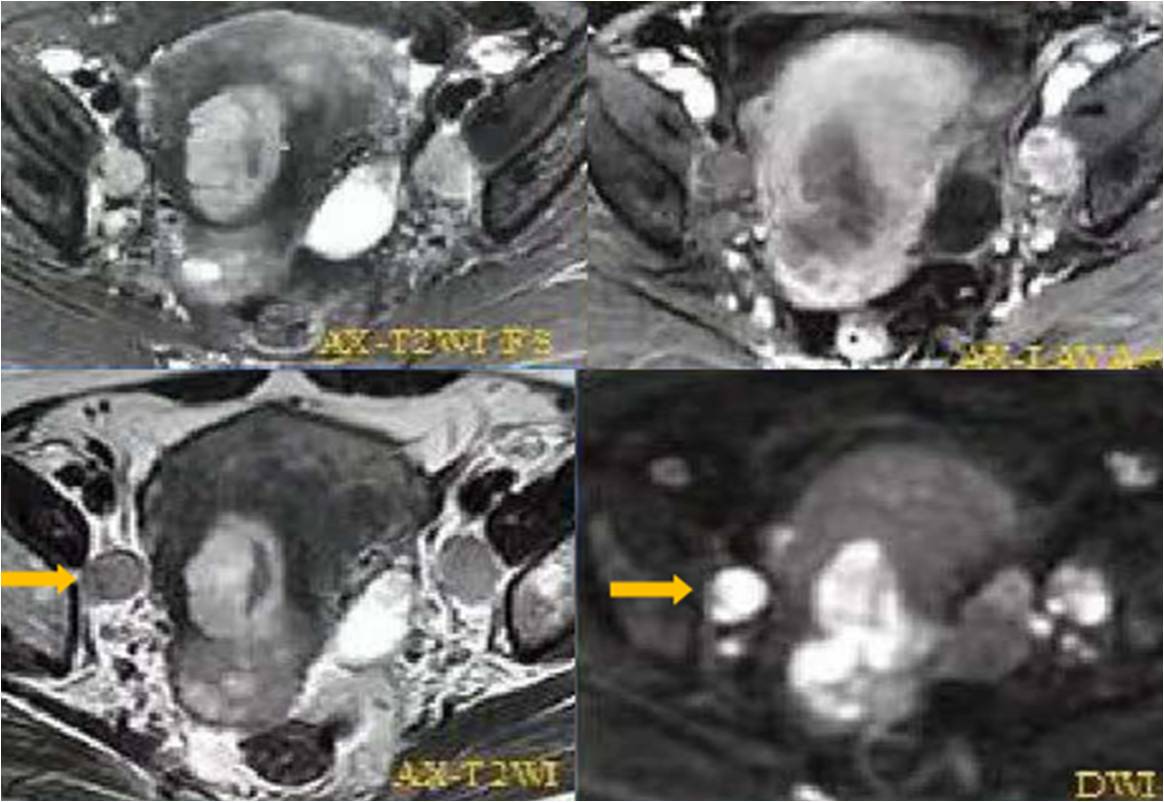

FIGO分期---子宮內膜癌

IA期 IB期 II期

III期 IV期

(三)子宮內膜癌分期思考

1. 宮頸是否受累影像判斷是難點(Ⅰ期還是Ⅱ期);

2. 關于淋巴結轉移:盆腔淋巴結轉移分ⅢC1,腹主動脈旁淋巴結轉移分ⅢC2,腹股溝淋巴結轉移屬于遠處轉移,應分ⅣB期;

3. 超出子宮范圍是Ⅲ期(輸卵管、卵巢/宮旁組織/陰道)。